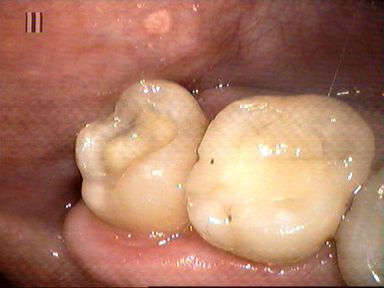

Odbudowa korony zęba trzonowego nakładem kompozytowym. Ząb przeleczono kanałowo i wzmocniono sztyftami z włókna szklanego.